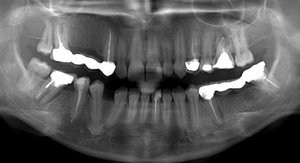

Из-за неправильного лечения образовалось воспаление под зубом и свищ сбоку на десне. В одной клинике сказали однозначно удалять, в другой, что есть 5% из 100, что можно как-то его спасти, но вряд ли.

Подскажите, пожалуйста, возможно ли вылечить зуб? Избавиться от гнойника вокруг него, чтобы не удалять зуб?

Однозначно зуб удаляется, нет там никаких пяти процентов успеха. Проблема связана, как с корнем зуба, так и по бифуркации.